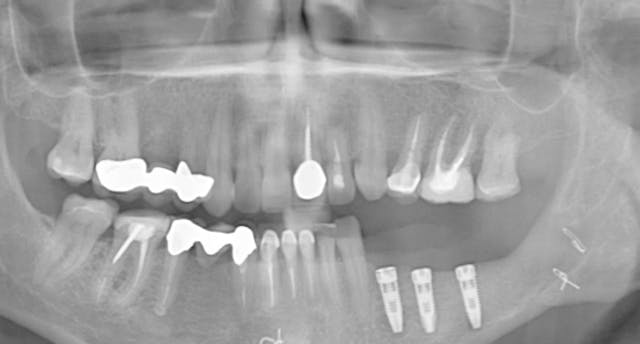

CLINICAL VIDEO All-on-4 Upper Jaw Implant Surgery - Patient consultation, oral e

IMPLANT DENTISTRY • 17m